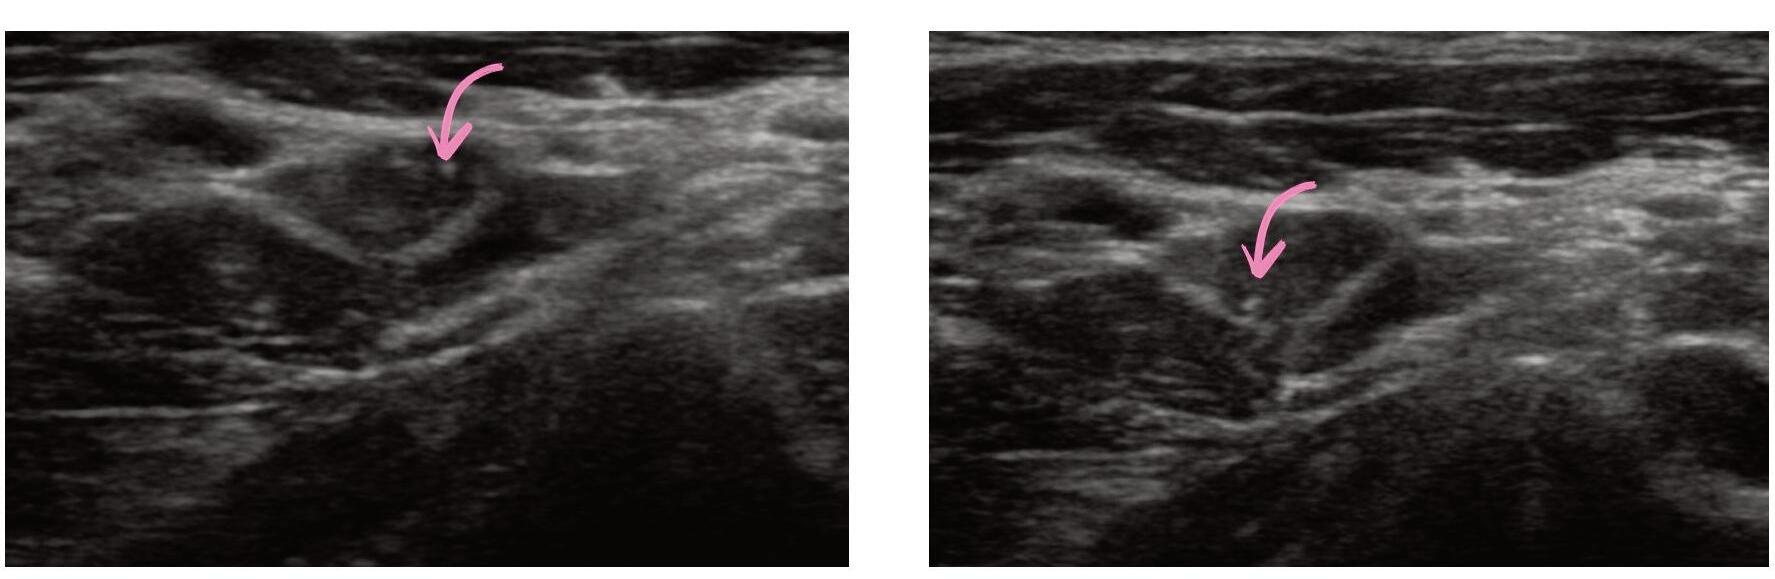

ECOGRAFIA DEL COLLO: STRUMENTO CHIAVE PER LA DIAGNOSI E IL MONITORAGGIO DEL CARCINOMA PAPILLARE DELLA TIROIDE

Giorgio Grani, Antonio Brunetti, Piernicola Garofalo, Giovanni Savoia, Michela Massa, Umberto Crocetti